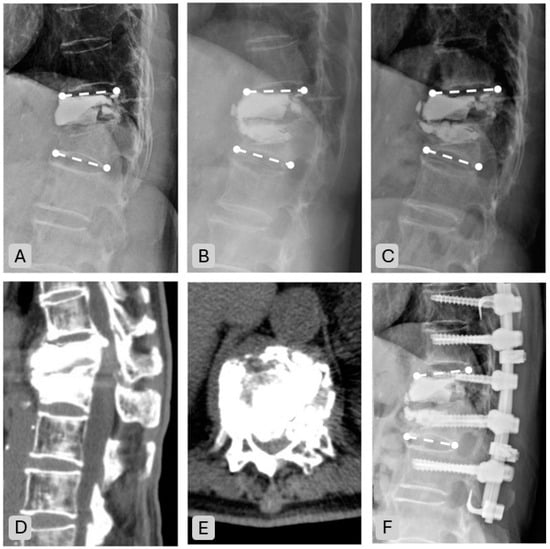

| Complication Type | n (%) |

|---|---|

| Nonunion | 3 (7.3) |

| New onset fracture | 4 (9.8) |

| Adjacent | 3 (7.3) |

| Remote | 1 (2.4) |

| Cement leakage | 4 (9.8) |

| Disc leakage | 2 (4.9) |

| Vessel leakage | 2 (4.9) |

| New neurologic deficits | 3 (7.3) |

| Spinal stenosis | 2 (4.9) |

| Persistent back pain | 1 (2.4) |

| Re-operation | 3 (7.3) |